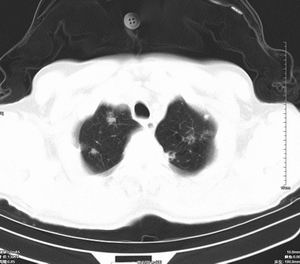

男 60岁,咳嗽,胸疼半年,请各位老师讨论.

肺内多发小结节,部分内见空泡,边界大部分清楚.多考虑:1 韦格氏肉芽肿.2 肺泡癌伴肺内转移不除外.

肺内多发结节样病灶,部分内见空泡影,边界大部分清楚,多考虑:

1.金葡菌感染

2 转移不除外

影像学表现:文献报告肺部浸润性见于50-65%的病人,肺部均有浸润,表现为肺内多发或单发结节影,出现多发厚壁空洞,内壁粗糙,易合并细菌性肺炎,也可出现胸腔积液。ct及hrct扫描可见大小不等的结节多分布于肺周边部,结节可呈楔形贴近胸膜,另一主要特征是其周围有线状斑痕影,即长毛刺征,受累血管及血管周围纤维化是其形成的原因,如累及胸膜尚可出现胸膜凹陷征。71%ct比胸片发现更多更小病灶, 典型的征象滋养血管征仅能在ct上显示。ct及hrct可检出典型影像征象。为诊断提供了重要依据,ct可成为肺韦格氏肉芽肿首选检查方法。

鉴别诊断:韦格氏肉芽肿ct表现与肺有关病变相似。如脓毒性肺栓塞的ct表现包括多发性,并有滋养血管的空洞性结节。滋养血管征也常见于肺梗塞和血行转移瘤。另外部灶呈楔形贴附胸膜面也是梗塞和脓毒性肺栓塞的ct特点之一。但肺梗塞和脓毒性肺梗塞的临床表现较急、全身或局部症状明显,另外肺结节边缘长毛刺征及胸膜凹陷征是上述病变所缺乏的,有助于本病的诊断和鉴别诊断。所以本病例应考虑肺转移。